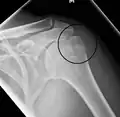

Proximal

Proximal humerus fractures most often occur among elderly people with osteoporosis who fall on an outstretched arm.[9] Less frequently, proximal fractures occur from motor vehicle accidents, gunshots, and violent muscle contractions from an electric shock or seizure.[10][5] Other risk factors for proximal fractures include having a low bone mineral density, having impaired vision and balance, and tobacco smoking.[11] A stress fracture of the proximal and shaft regions can occur after an excessive amount of throwing, such as pitching in baseball.[6]